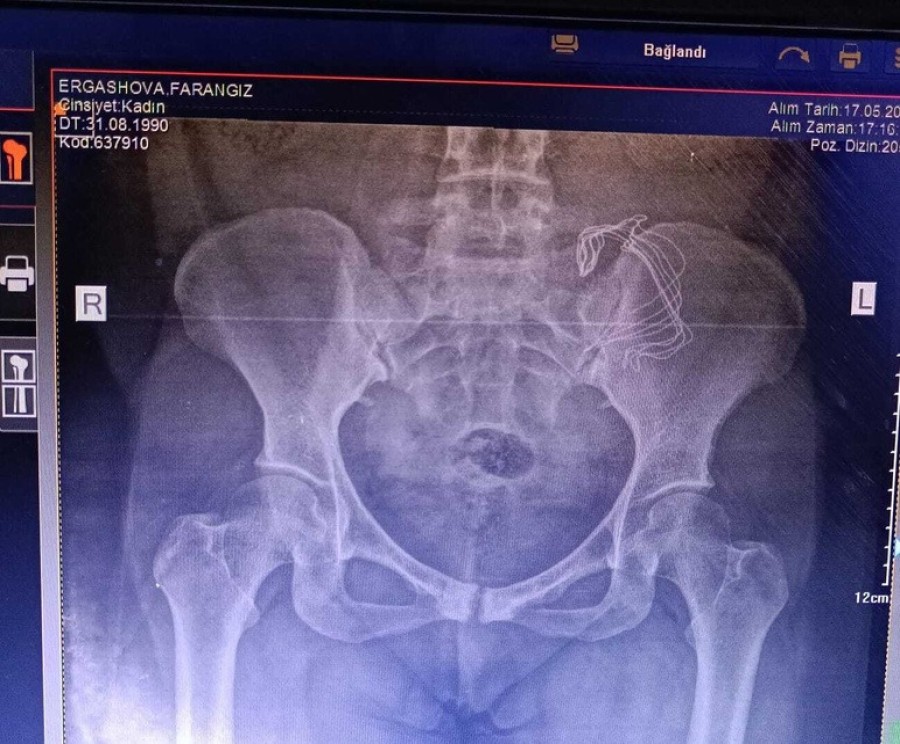

Ağrıları artarak devam eden Ergashova, geçtiğimiz Mayıs ayında farklı bir hastaneye başvurdu. Şikayetlerini doktora anlatan Ergashova'dan tomografi çektirilmesi istendi. Tomografiye bakan doktor, Ergashova'nın karnın sol tarafında yabancı bir cisim olduğunu fark etti. Sonuçlardan sonra Ergashova'nın karnındaki cisim 10 ay sonra ameliyat ile alındı.

Hastanede yapılan kontrollerde ve çekilen tomografide sonra Frangiz Ergashova ameliyata alındı. Ameliyattan sonra Ergashova'nın karnında doğum sonrası unutulan 15 santimetre büyüklüğünde gazlı bez olduğu ortaya çıktı. Frangiz Ergashova, 10 aydır yaşadığı ağrılara ihmalin neden olduğunu öğrendi. Umut Can ismini verdikleri oğlunun doğumdan sonra 12 gün boyunca küvezde kaldığını söyleyen aile, durumunun şu an iyi olduğunu belirterek hastaneden ve doktordan şikayetçi oldu.

Ameliyatta sargı bezi gibi bir şey çıktı ve iltihaplanmış. 15 cm sargı bezi var dediler. Sargı beziyle gezmişim, İçimde iltihaplanmış. İki çocuğum annesiz kalabilirdi. Ölümden döndüm diyebilirim."